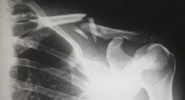

Японские ученые из Осакского университета разработали метод быстрого заживления переломов с помощью плазменного облучения.Газета.Ru

Метод протестировали на лабораторных крысах с переломами двух типов: обычным и сложным со смещением костей.Pro город будущего

Затем места травм некоторых животных подвергли воздействию холодной плазмы под давлением в одну атмосферу.Газета.Ru